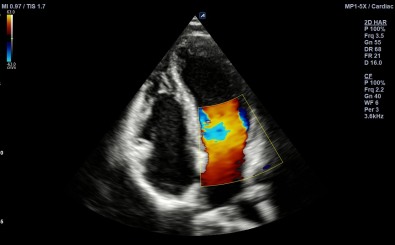

Cardiac